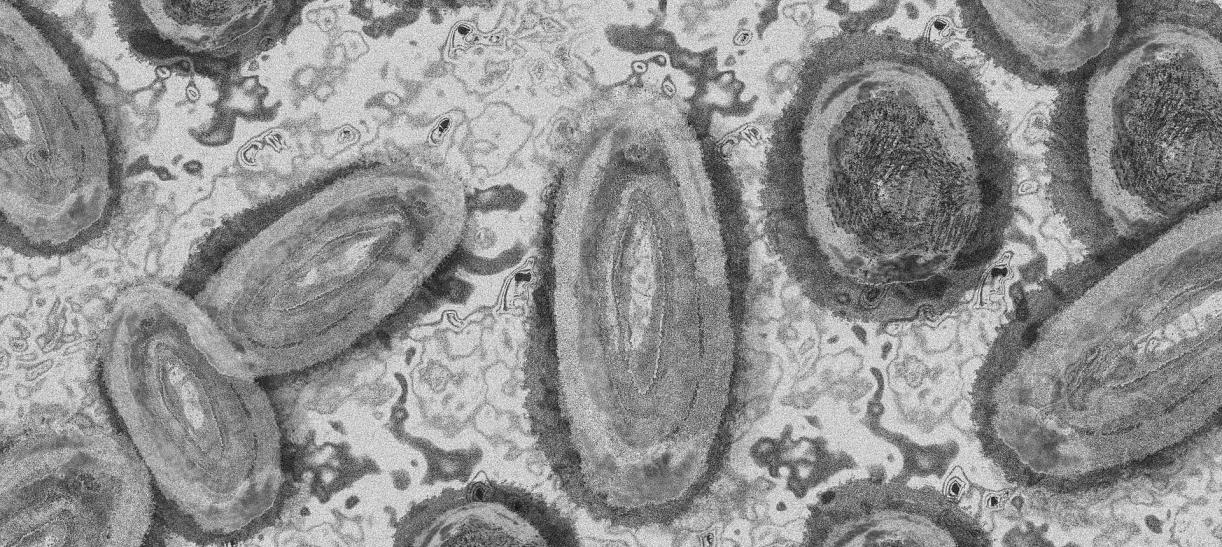

A diez ascienden los contagios de viruela símica en Colombia

El Instituto Nacional de Salud y la Secretaría Distrital de Salud reportaron tres nuevos casos de viruela símica en el país.

Los casos identificados se encuentran en Bogotá y uno en Medellín. Ocho de las personas contagiadas tienen antecedente de viaje a Europa o Estados Unidos y dos son contactos de viajeros procedentes de esos dos lugares. A la fecha, en total son 10 los colombianos que han contraído este virus.